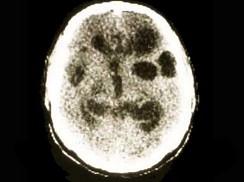

问题 参考下图,猪囊尾蚴寄生于人脑部可引起脑囊尾蚴病。依据临床表现的不同,脑囊尾蚴病可以分为 ( )

选项 A.脑实质型 B.脑室型 C.软脑膜型 D.小脑型 E.脊髓型

答案 ABCE